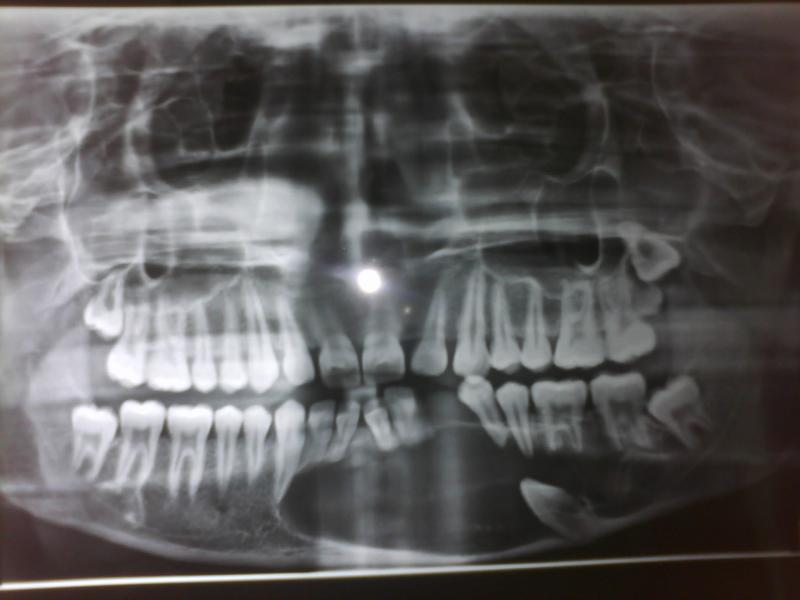

Case of Ameloblastoma